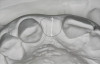

Figure 7  These images summarize the various dimensional assessments that underscore the Rules of Six guidelines, which enable simple planning for uncomplicated single-tooth dental implant therapy: Finding mesiodistal or inter-radicular (Fig 7), buccolingual (Fig 8), and inter-occlusal (Fig 9) distances of 6 mm can assure uncomplicated implant placement and restoration.

Figure 7

Figure 8  These images summarize the various dimensional assessments that underscore the Rules of Six guidelines, which enable simple planning for uncomplicated single-tooth dental implant therapy: Finding mesiodistal or inter-radicular (Fig 7), buccolingual (Fig 8), and inter-occlusal (Fig 9) distances of 6 mm can assure uncomplicated implant placement and restoration.

Figure 8

Figure 9: These images summarize the various dimensional assessments that underscore the Rules of Six guidelines, which enable simple planning for uncomplicated single-tooth dental implant therapy: Finding mesiodistal or inter-radicular (Fig 7), buccolingual (Fig 8), and inter-occlusal (Fig 9) distances of 6 mm can assure uncomplicated implant placement and restoration.

Figure 9